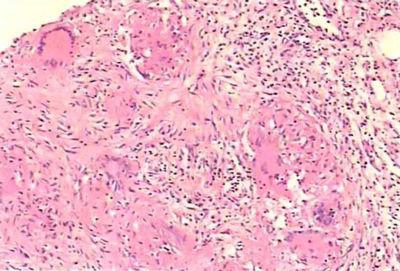

結(jié)核球又名結(jié)核瘤,是與周圍組織境界分明的球形干酪樣壞死灶。鏡下觀,結(jié)核瘤的中心部有程度不等的干酪樣壞死灶,有的已發(fā)生鈣化,周圍可見有Langhans巨細(xì)胞及類上皮細(xì)胞的結(jié)核性肉芽組織。